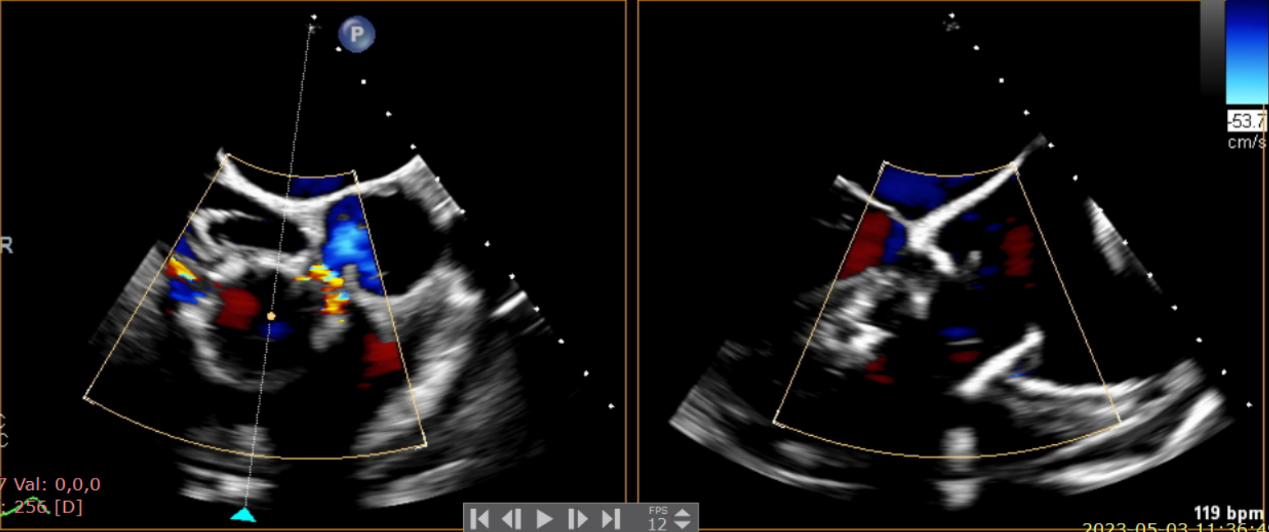

術前超聲提示大量三尖瓣反流

術中輸送器在超聲引導下調整位置

術后超聲提示僅殘余輕微瓣周漏